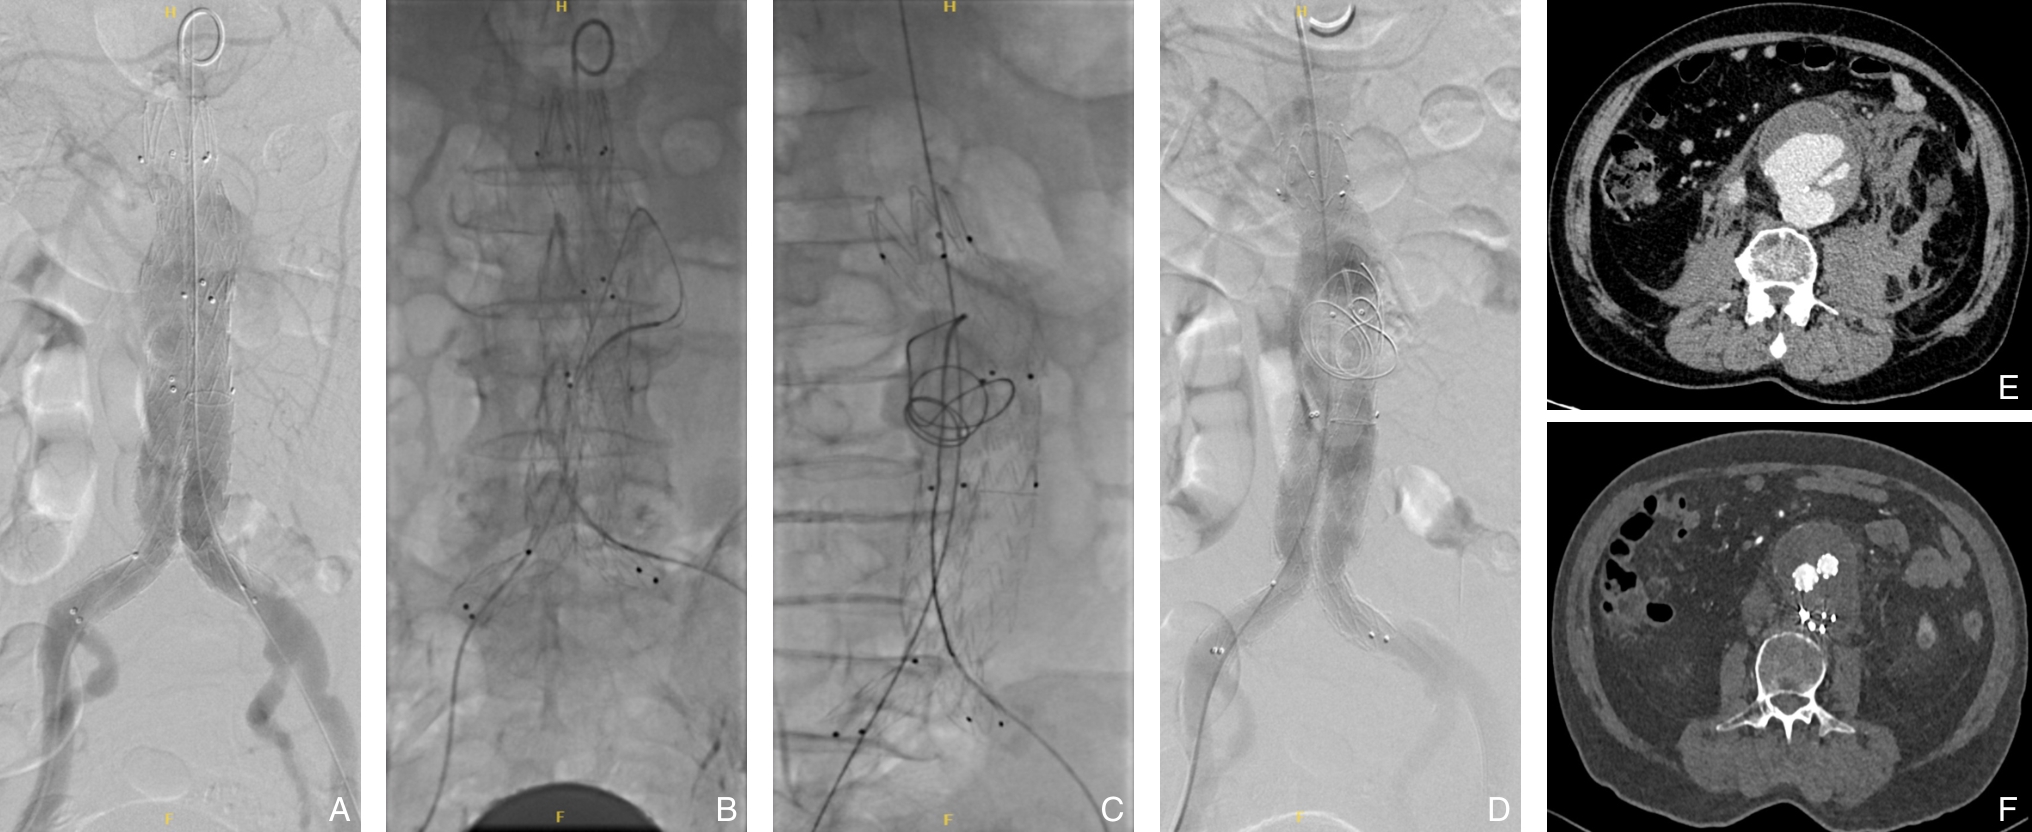

摘要:背景与目的 自发性孤立性肠系膜上动脉夹层(SISMAD)是一种较为常见的内脏动脉夹层疾病,主要表现为急性腹痛,严重者可引发肠缺血甚至坏死。随着CT血管成像(CTA)等影像技术的普及,SISMAD的检出率显著提高,但目前针对其治疗策略仍存在争议,尤其在保守治疗与腔内介入治疗之间的选择缺乏统一标准。为探讨两种治疗方式的临床效果及适应人群,本研究回顾性分析本中心SISMAD患者的临床资料,并比较不同治疗方式的短中期疗效,为制定个体化治疗策略提供依据。方法 回顾性分析2018年1月—2023年12月浙江省宁波市第二医院确诊的174例SISMAD患者临床资料,其中保守治疗30例,腔内介入治疗144例(包括支架植入和部分假腔弹簧圈栓塞联合支架植入)。术前均行CTA或肠系膜上动脉造影并分型。随访评估患者术后1个月和1年症状缓解情况及影像学指标,包括夹层重塑率、支架通畅性等。结果 保守治疗组1个月症状缓解率为90.0%,1年为92.8%;介入治疗组分别为99.3%和98.6%。1个月症状缓解率差异具有统计学意义(P=0.016),1年症状缓解率差异无统计学意义(P>0.05)。分型亚组比较中,介入治疗组各型症状缓解率普遍高于保守治疗,但差异均无统计学意义(均P>0.05);保守治疗组Ⅲ型患者症状控制较差,出现死亡病例。介入治疗成功率为99.3%,1年内支架移位或闭塞为0例,完全重塑率为86.8%,支架通畅率为100%。部分患者支架内出现少量附壁血栓,未见血流阻断。结论 腔内介入治疗对SISMAD患者具有较高的技术成功率和良好的短中期疗效,尤其适用于真腔血流受限的Ⅱ型及Ⅲ型患者。建议根据夹层分型及血流受限程度,个体化制定治疗方案,以提升疗效、降低风险。

摘要:背景与目的 腹主动脉瘤(AAA)是血管外科常见的动脉扩张性疾病,其最严重的并发症为瘤体破裂,常引发致命性大出血,严重威胁患者生命安全。腹主动脉瘤腔内修复术(EVAR)因其微创、安全、恢复快的优势,已成为AAA的首选治疗方式。然而,术后特有的内漏并发症仍是当前临床面临的主要难题。内漏可致瘤腔持续高压,增加瘤体扩张及破裂风险,是EVAR术后二次干预率较高的主要原因之一,尤其Ⅱ型内漏的处理策略尚存争议。本研究旨在评估在标准EVAR术中联合经髂动脉入路选择性瘤囊栓塞技术治疗即刻内漏的临床应用价值。 方法 回顾性收集2023年3月—2024年9月在中国医科大学附属第一医院接受标准EVAR治疗并有内漏风险的AAA患者临床资料。根据是否实施术中经髂动脉入路选择性瘤囊栓塞分为干预组(42例)与未干预组(32例),比较两组患者的一般资料、术前AAA解剖学特征、手术细节及术后随访结果。 结果 两组患者在年龄、性别、解剖特征、破裂率及超说明书使用比例等方面差异无统计学意义(均 P>0.05)。两组术中技术成功率均为100%。干预组1例术后出现一过性乙状结肠缺血,经保守治疗好转。平均随访时间为(6.49±4.68)个月,干预组瘤囊缩小、稳定及增大比例分别为40.5%、57.1%和2.4%,未干预组分别为59.4%、40.6%和0.0%,两组间差异无统计学意义(均 P>0.05)。随访期间内漏发生率在两组间亦无明显差异( P>0.05)。 结论 对于标准EVAR术中出现的内漏,经髂动脉入路选择性瘤囊栓塞技术操作简便、安全,短期疗效与术中无内漏者相当,值得临床推广。其远期疗效仍需进一步随访验证。